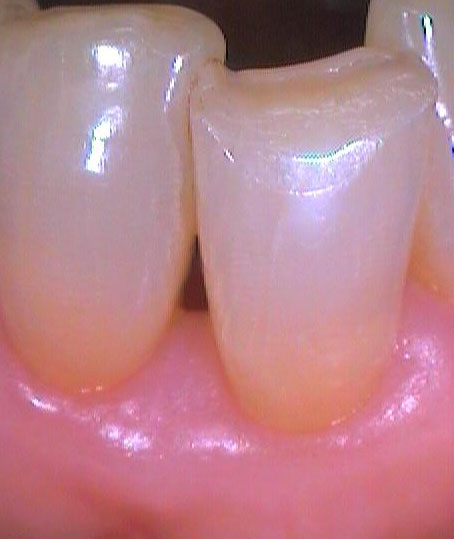

Втори случай

Преди почистване на зъбния камък